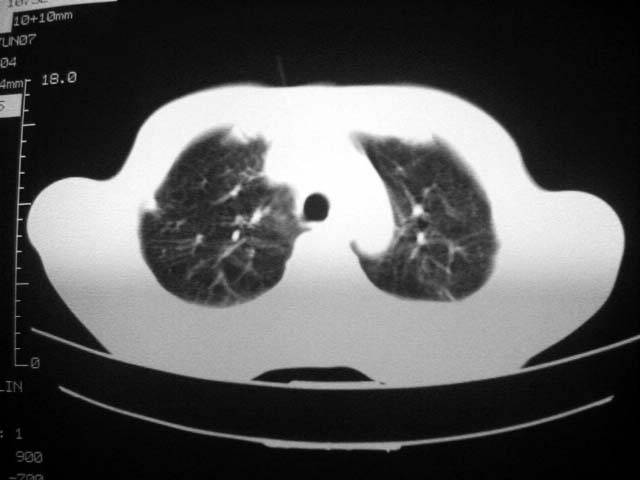

患者现无咳嗽咳痰及咳血,肝功好转,血清白蛋白降低,球蛋白升高,白球比小于0.5.少量腹水。

回顾既往片,病变明显吸收,缩小,未经治疗,不支持肺转移瘤,可能为肺结节病或韦格氏肉芽肿

支持韦格氏肉芽肿

患者近期复查胸ct正常,轻度肝功异常,保肝、抗病毒(拉美夫叮)治疗中。